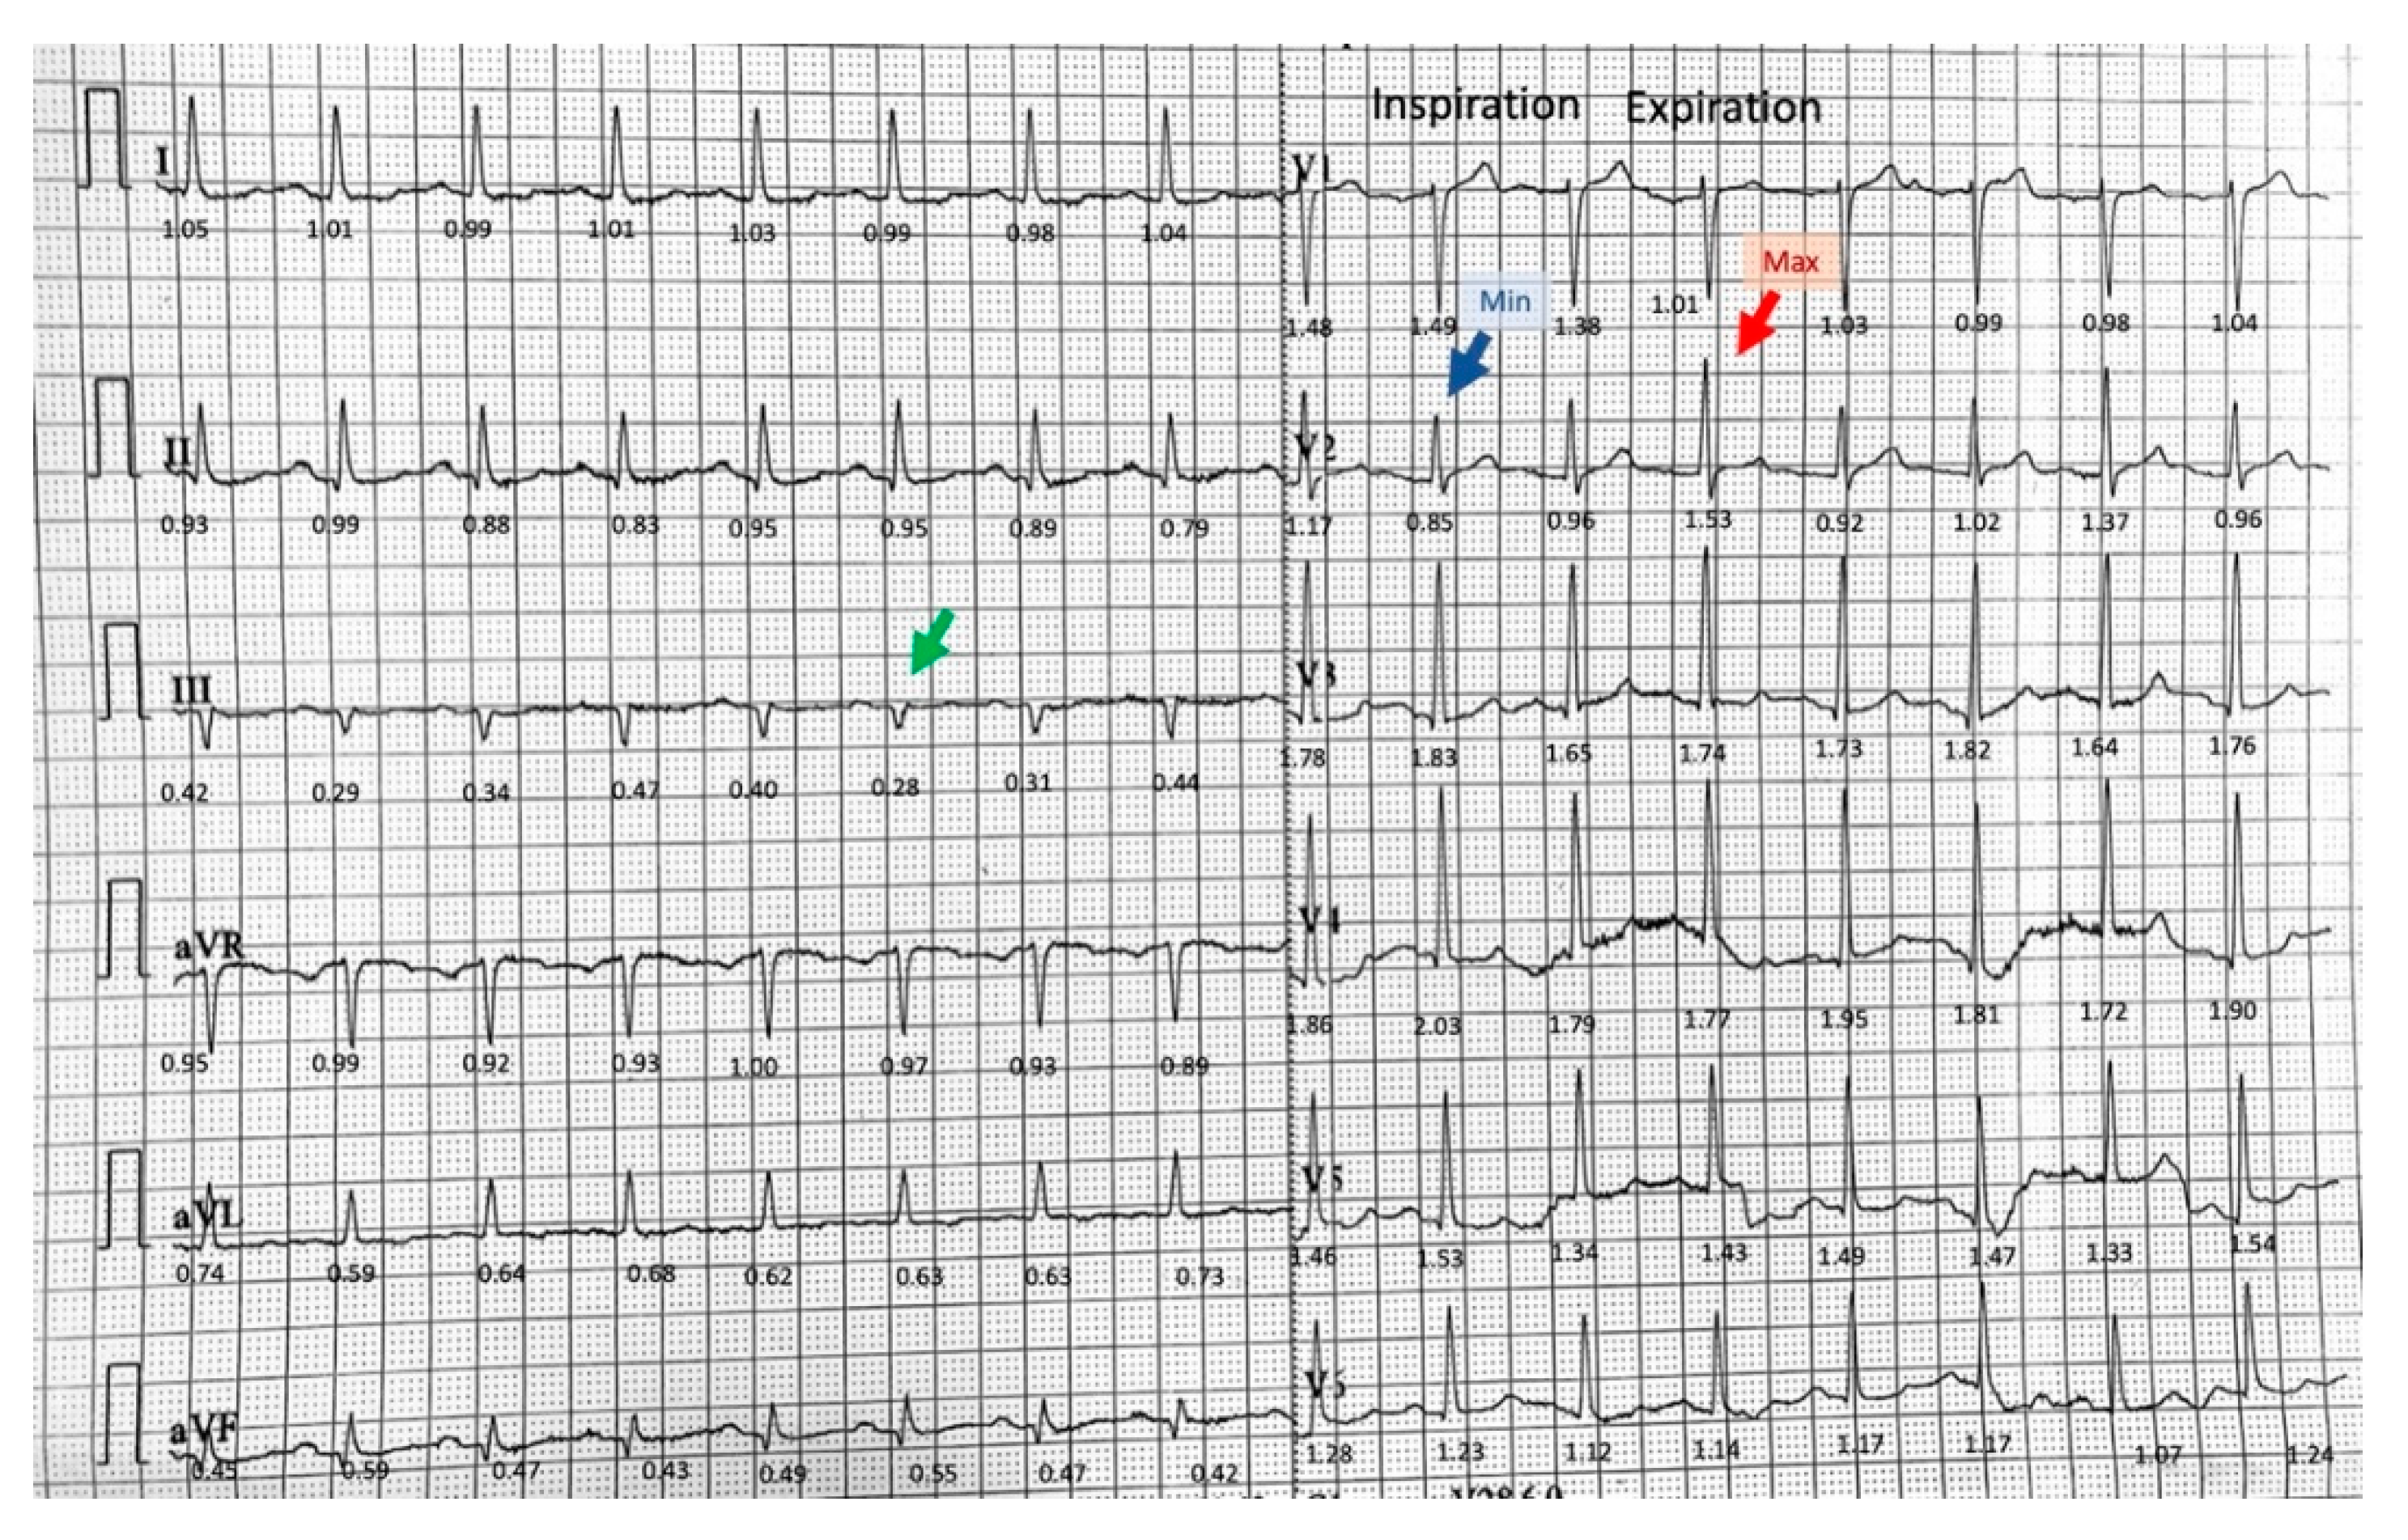

3.1. Phasic Variations in the QRS Complex Amplitude